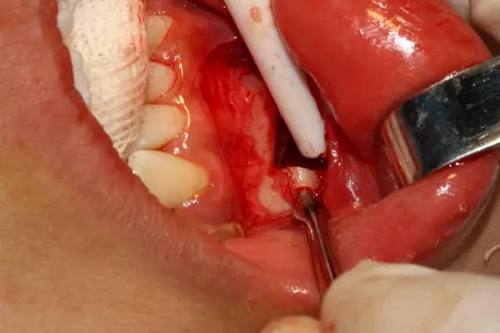

去除骨皮質(zhì),暴露牙冠大部分

設(shè)計(jì)冠切的位置

橫斷牙冠,注意深度的把控